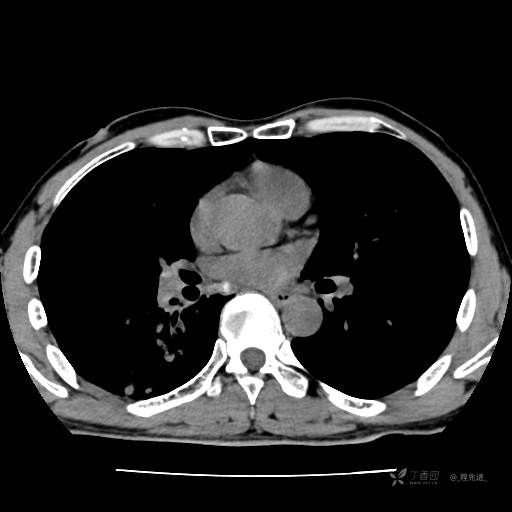

辅助检查:我院门诊胸部CT示:如下。心电图:窦性心律;正常心电图。